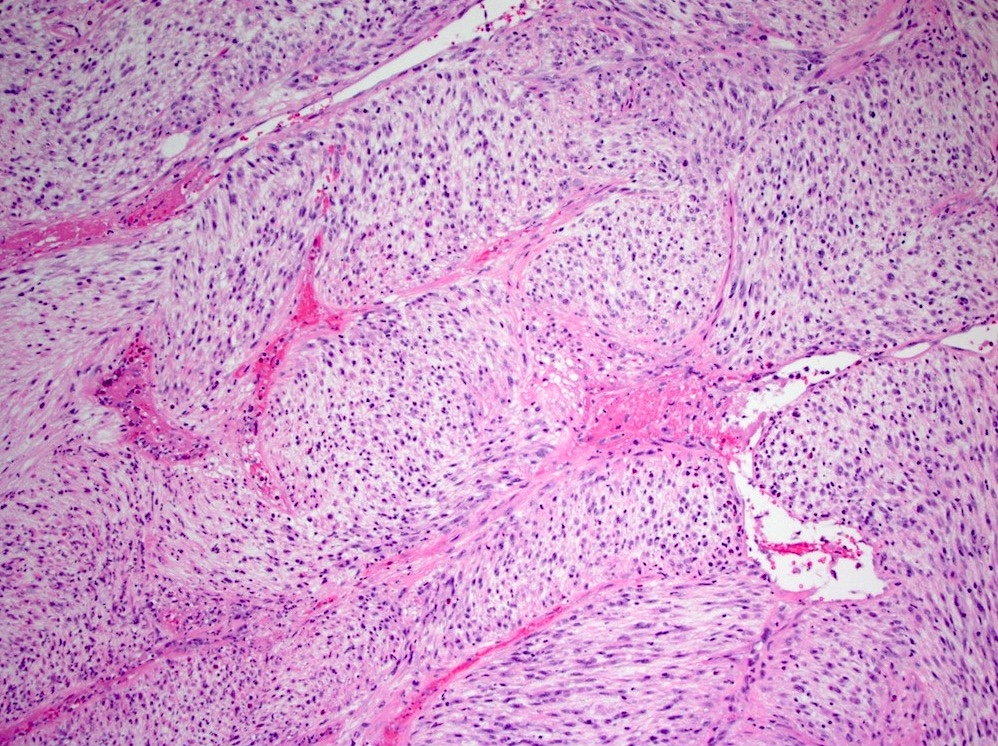

Microscopic (histologic) description

- Bland spindle cells with abundant amphophilic cytoplasm and variably prominent nucleoli

- Lymphoplasmacytic infiltrate with polyclonal plasma cells

- Background may show myxoid change or laminated / whorled fibrosis

- Epithelioid inflammatory myofibroblastic sarcoma: similar, except cells are more epithelioid, with large nucleoli

Microscopic (histologic) images

Contributed by Raul S. Gonzalez, M.D.